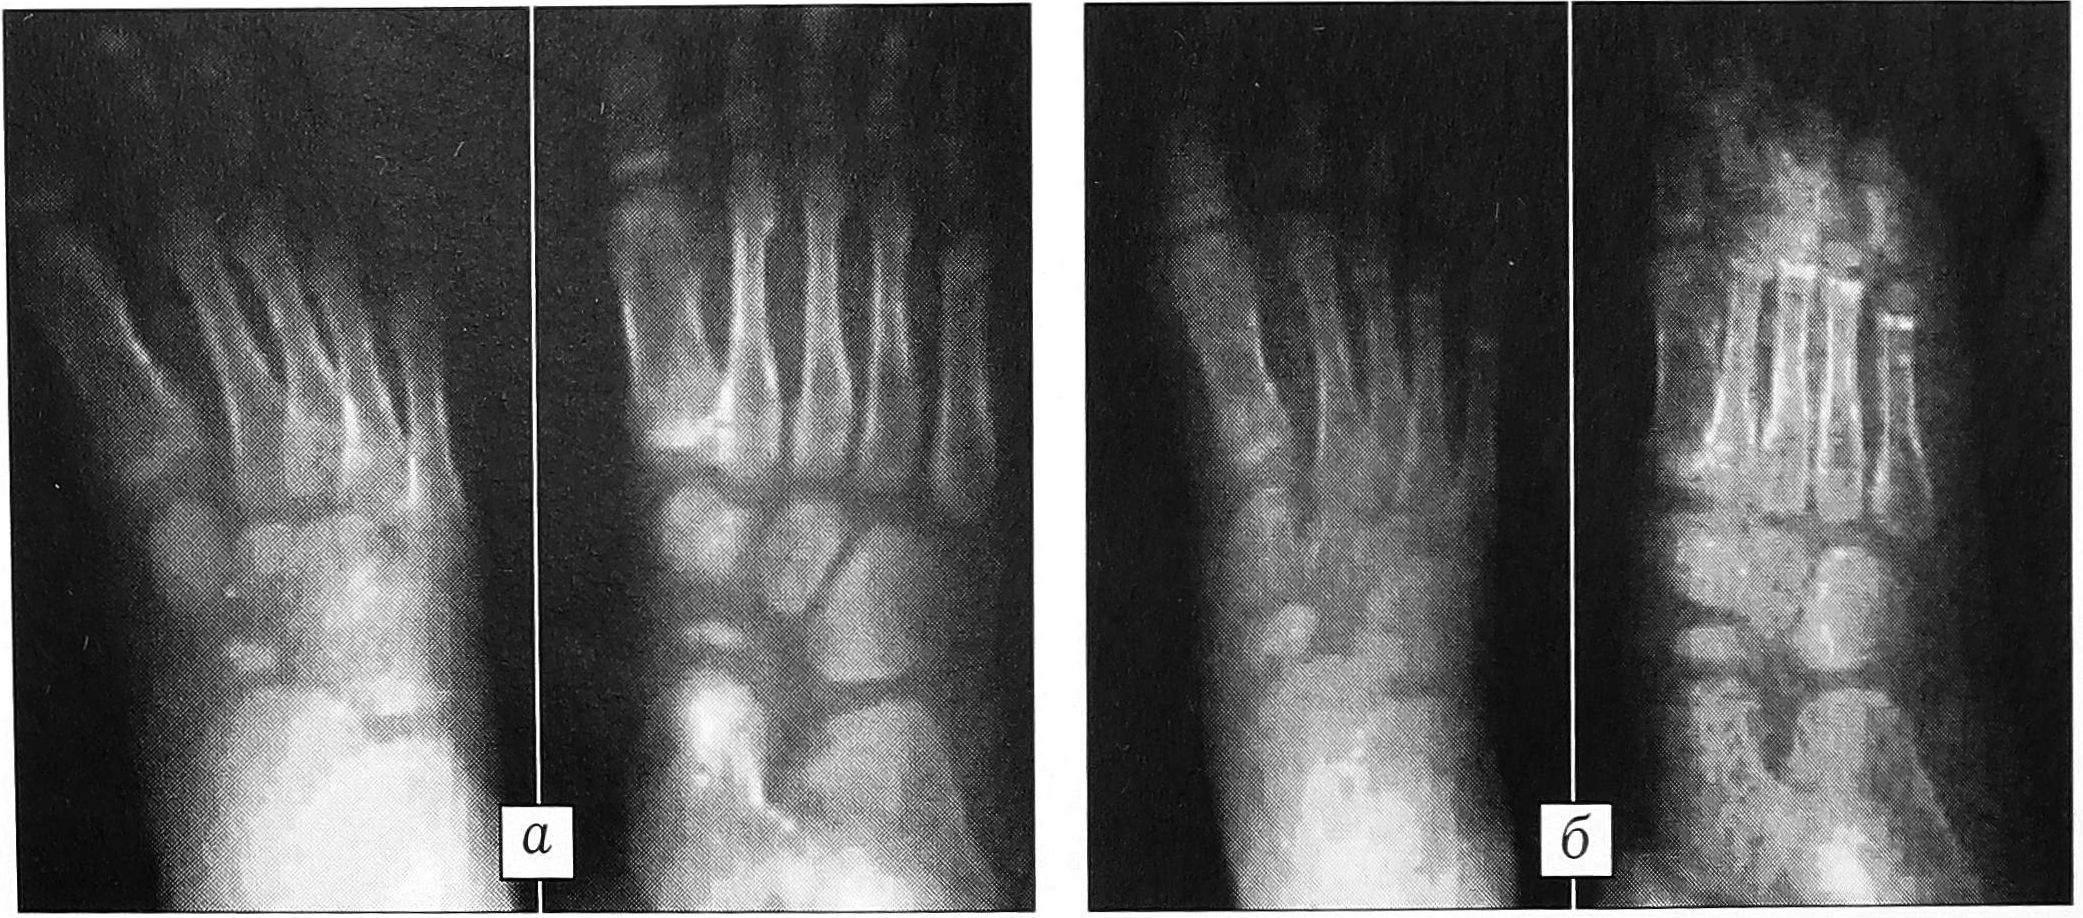

Клинический пример. Больной Л ., 12 лет. Диагноз: болезнь Келера 1 справа (рис. 2, а). Болевой синдром в течение года. По месту жительства на протяжении полугода получал консервативное лечение, не давшее эффекта. В клинике детской ортопедии ЦИТО произведена туннелизация области остеохондропатии с введением жидкой полимерной композиции. Боли прошли в течение 1 мес после операции. Через 12 мес рентгенологически констатировано восстановление формы и структуры кости (рис. 2, б). Результат лечения расценен как отличный.

Рис. 2. Больной Л. 12 лет. Диагноз: болезнь Келера 1 справа. а — рентгенограммы до лечения: деструкция ладьевидной кости с признаками фрагментации; б — рентгенограммы через 12 мес после введения биоактивной композиции ППМ-1: восстановление структуры ладьевидной кости.